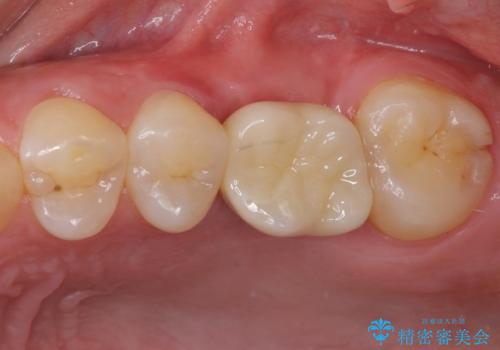

痛みがないので、ボロボロのまま放置していましたが、抜歯後は汚れが溜まりにくくなりスッキリとしたようです。

前歯のデコボコも解消され、ブラッシングが楽になりました。